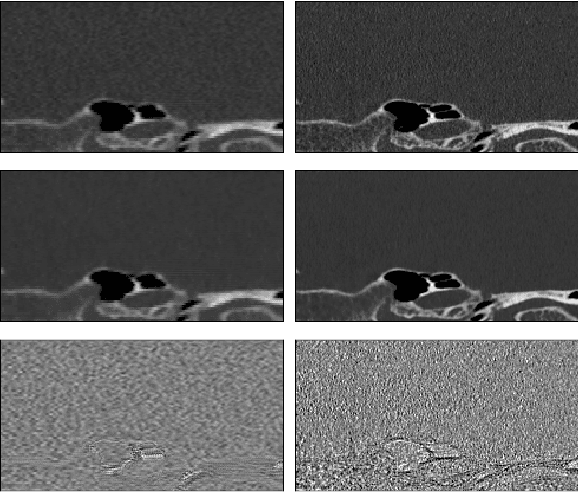

Abstract:Ultra-high resolution images are desirable in photon counting CT (PCCT), but resolution is physically limited by interactions such as charge sharing. Deep learning is a possible method for super-resolution (SR), but sourcing paired training data that adequately models the target task is difficult. Additionally, SR algorithms can distort noise texture, which is an important in many clinical diagnostic scenarios. Here, we train conditional denoising diffusion probabilistic models (DDPMs) for PCCT super-resolution, with the objective to retain textural characteristics of local noise. PCCT simulation methods are used to synthesize realistic resolution degradation. To preserve noise texture, we explore decoupling the noise and signal image inputs and outputs via deep denoisers, explicitly mapping to each during the SR process. Our experimental results indicate that our DDPM trained on simulated data can improve sharpness in real PCCT images. Additionally, the disentanglement of noise from the original image allows our model more faithfully preserve noise texture.